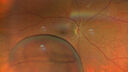

Chronic macula-splitting demarcated retinal detachment3 views35 year old female with 20/25 vision and noticing something wrong with the superior vision in the right eye for a long time.Apr 13, 2026